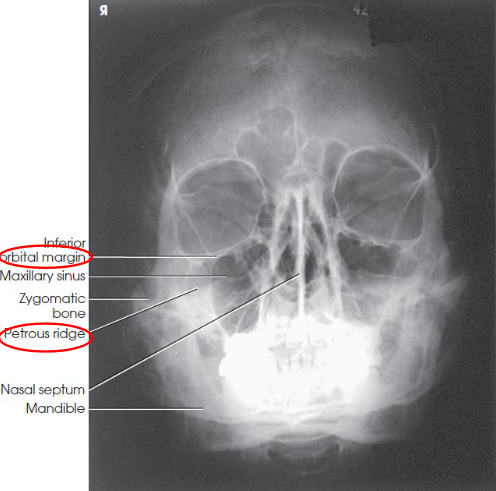

Modified parietoacanthial (modified Waters) facial bones image criteria

facial bones with less axial angulation than Waters method

petrous ridges projected just below the inferior border of the orbits at a level midway through the maxillary sinuses

orbital floor seen perpendicular to the IR and parallel to the CR

demonstrates inferior displacement of the orbital flooropacified maxillary sinus